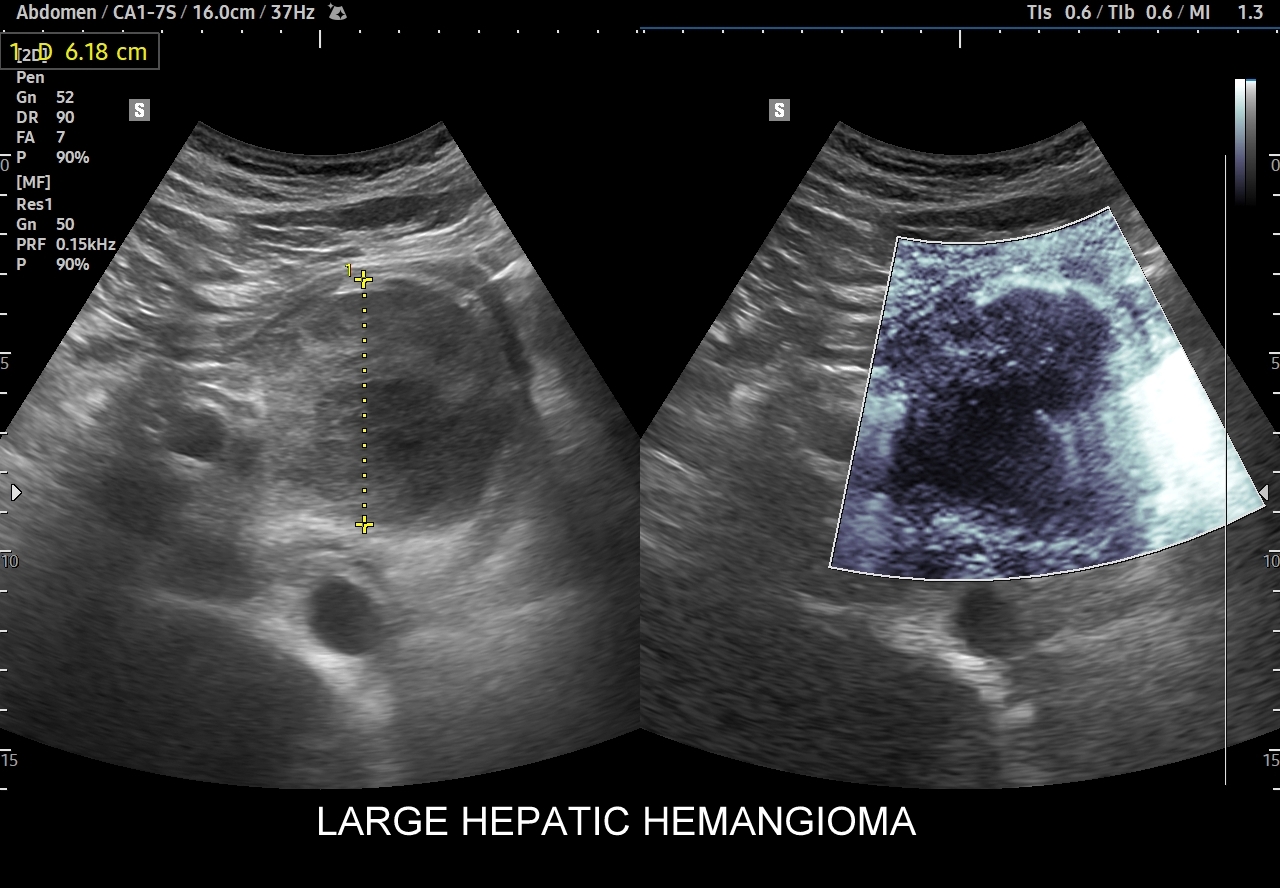

Naczyniaki duże, tj. powyżej 2-3 cm, mogą mieć strukturę niejednorodną echogenicznie, w tym obszary hypoechogenne. Spotyka się także naczyniaki o charakterystyce normo- lub hypechogenicznej, w szczególności w wątrobie stłuszczonej. Z powyższych względów należy mieć na uwadze i zapamiętać, że badanie USG w podstawowym trybie B nie jest wystarczające do postawienia rozpoznania naczyniaka wątroby. W ramach obrazowej diagnostyki różnicowej najbardziej pomocnym jest badanie USG z kontrastem (CEUS), w którym to naczyniak wątroby posiada charakterystyczny wzorzec wypełnienia.

Najbardziej charakterystyczną cechą naczyniaka wątroby w badaniu CEUS jest jego wypełnianie w postaci guzkowej (ang. peripheral nodular enhancement) od obwodu ku centrum zmiany (ang. centripetal). Szybkość wypełniania bywa różnorodna, może być powolna lub szybka. W przypadku szybkiego wypełniania (tzw. flash-filling), w celu wykazania charakterystycznego centrypetalnego wypełniania niezbędna może być postprocessing’owa analiza poklatkowa zapisanego nagrania badania. W fazie późnej naczyniak wątroby pozostaje izowzmocniony lub hyperwzmocniony w stosunku do natywnego miąższu wątroby.